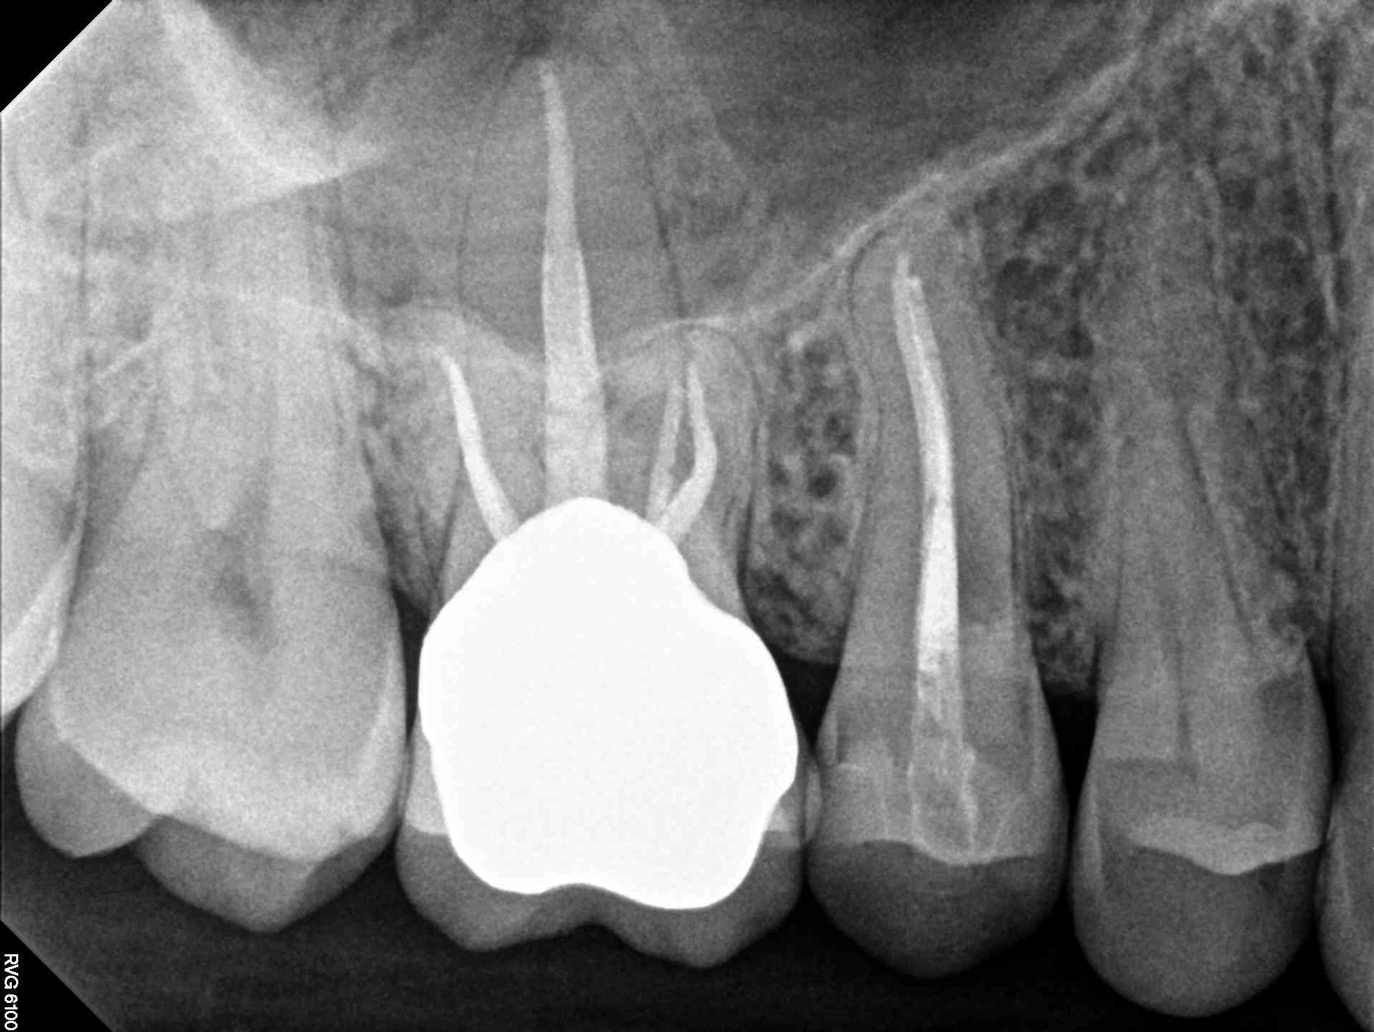

(2.) NSRCT, which had previously been completed on tooth No. 3, was also completed on tooth No. 4 prior to initiating surgical repair of the ECR lesions because it exhibited signs and symptoms of irreversible pulpitis.

Figure 2

If an ECR lesion is surgically accessible, external repair with gingival flap surgery is the treatment of choice (Figure 1 through Figure 6). When considering external repair, clinicians should evaluate each case for potential postoperative esthetic concerns, such as the possibility of recession following surgical repair.6,7 Moreover, clinicians should assess the overall restorability of affected teeth because the surgical repair of large ECR lesions may predispose them to fracture.6 When a Heithersay Class 1 lesion is diagnosed, nonsurgical root canal therapy (NSRCT) in addition to the surgical repair is often unnecessary. However, in Heithersay Class 2 or larger defects where pulpal involvement is suspected or confirmed, NSRCT may be necessary in addition to surgical repair.6 If NSRCT is indicated in addition to surgical repair, it is recommended that it be completed prior to surgery to avoid exacerbating pulpal disease.